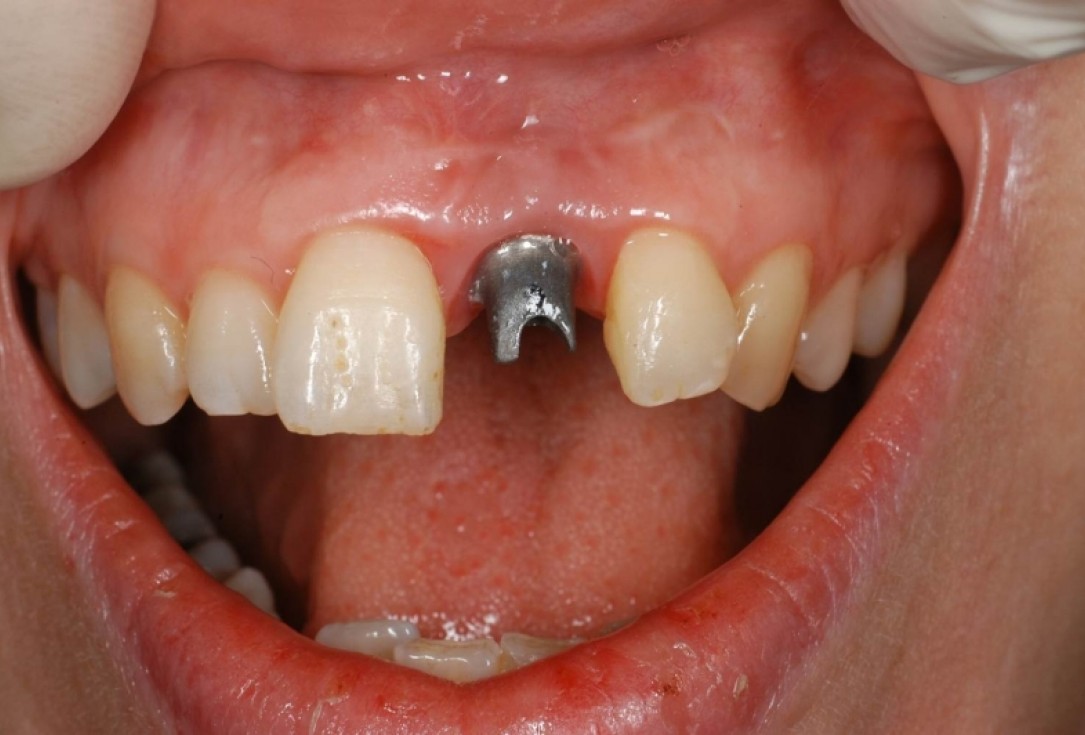

10/12 - Placement of abutment 6 months post-OPTreatment of dehiscence defect with cerabone® & Jason® membrane - Dr. M. Steigmann